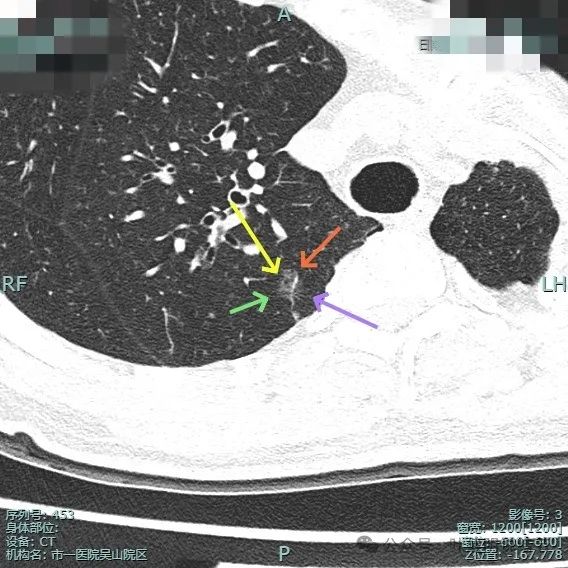

图片

主病灶术前定位,医用胶就在病灶边上(上图绿色的是定位医用胶,红色箭头指的是病灶6)。

次病灶术前定位,上图均是定位胶,结节太小,在其附近层面。